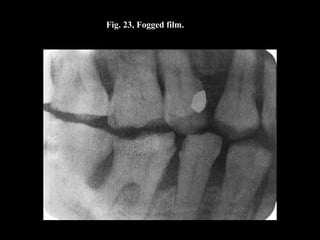

Fig. 23, Fogged film.

The Darkroom • Theterm “light-tight” is often used to describe the darkroom. • To be light-tight, no light leaks can be present. • When you are in the darkroom with the light turned off, no white light should be visible. • X-ray film is extremely sensitive to visible white light. • Any leakage of white light can cause film fog. A fogged film appears dull gray, lacks contrast, and is nondiagnostic.